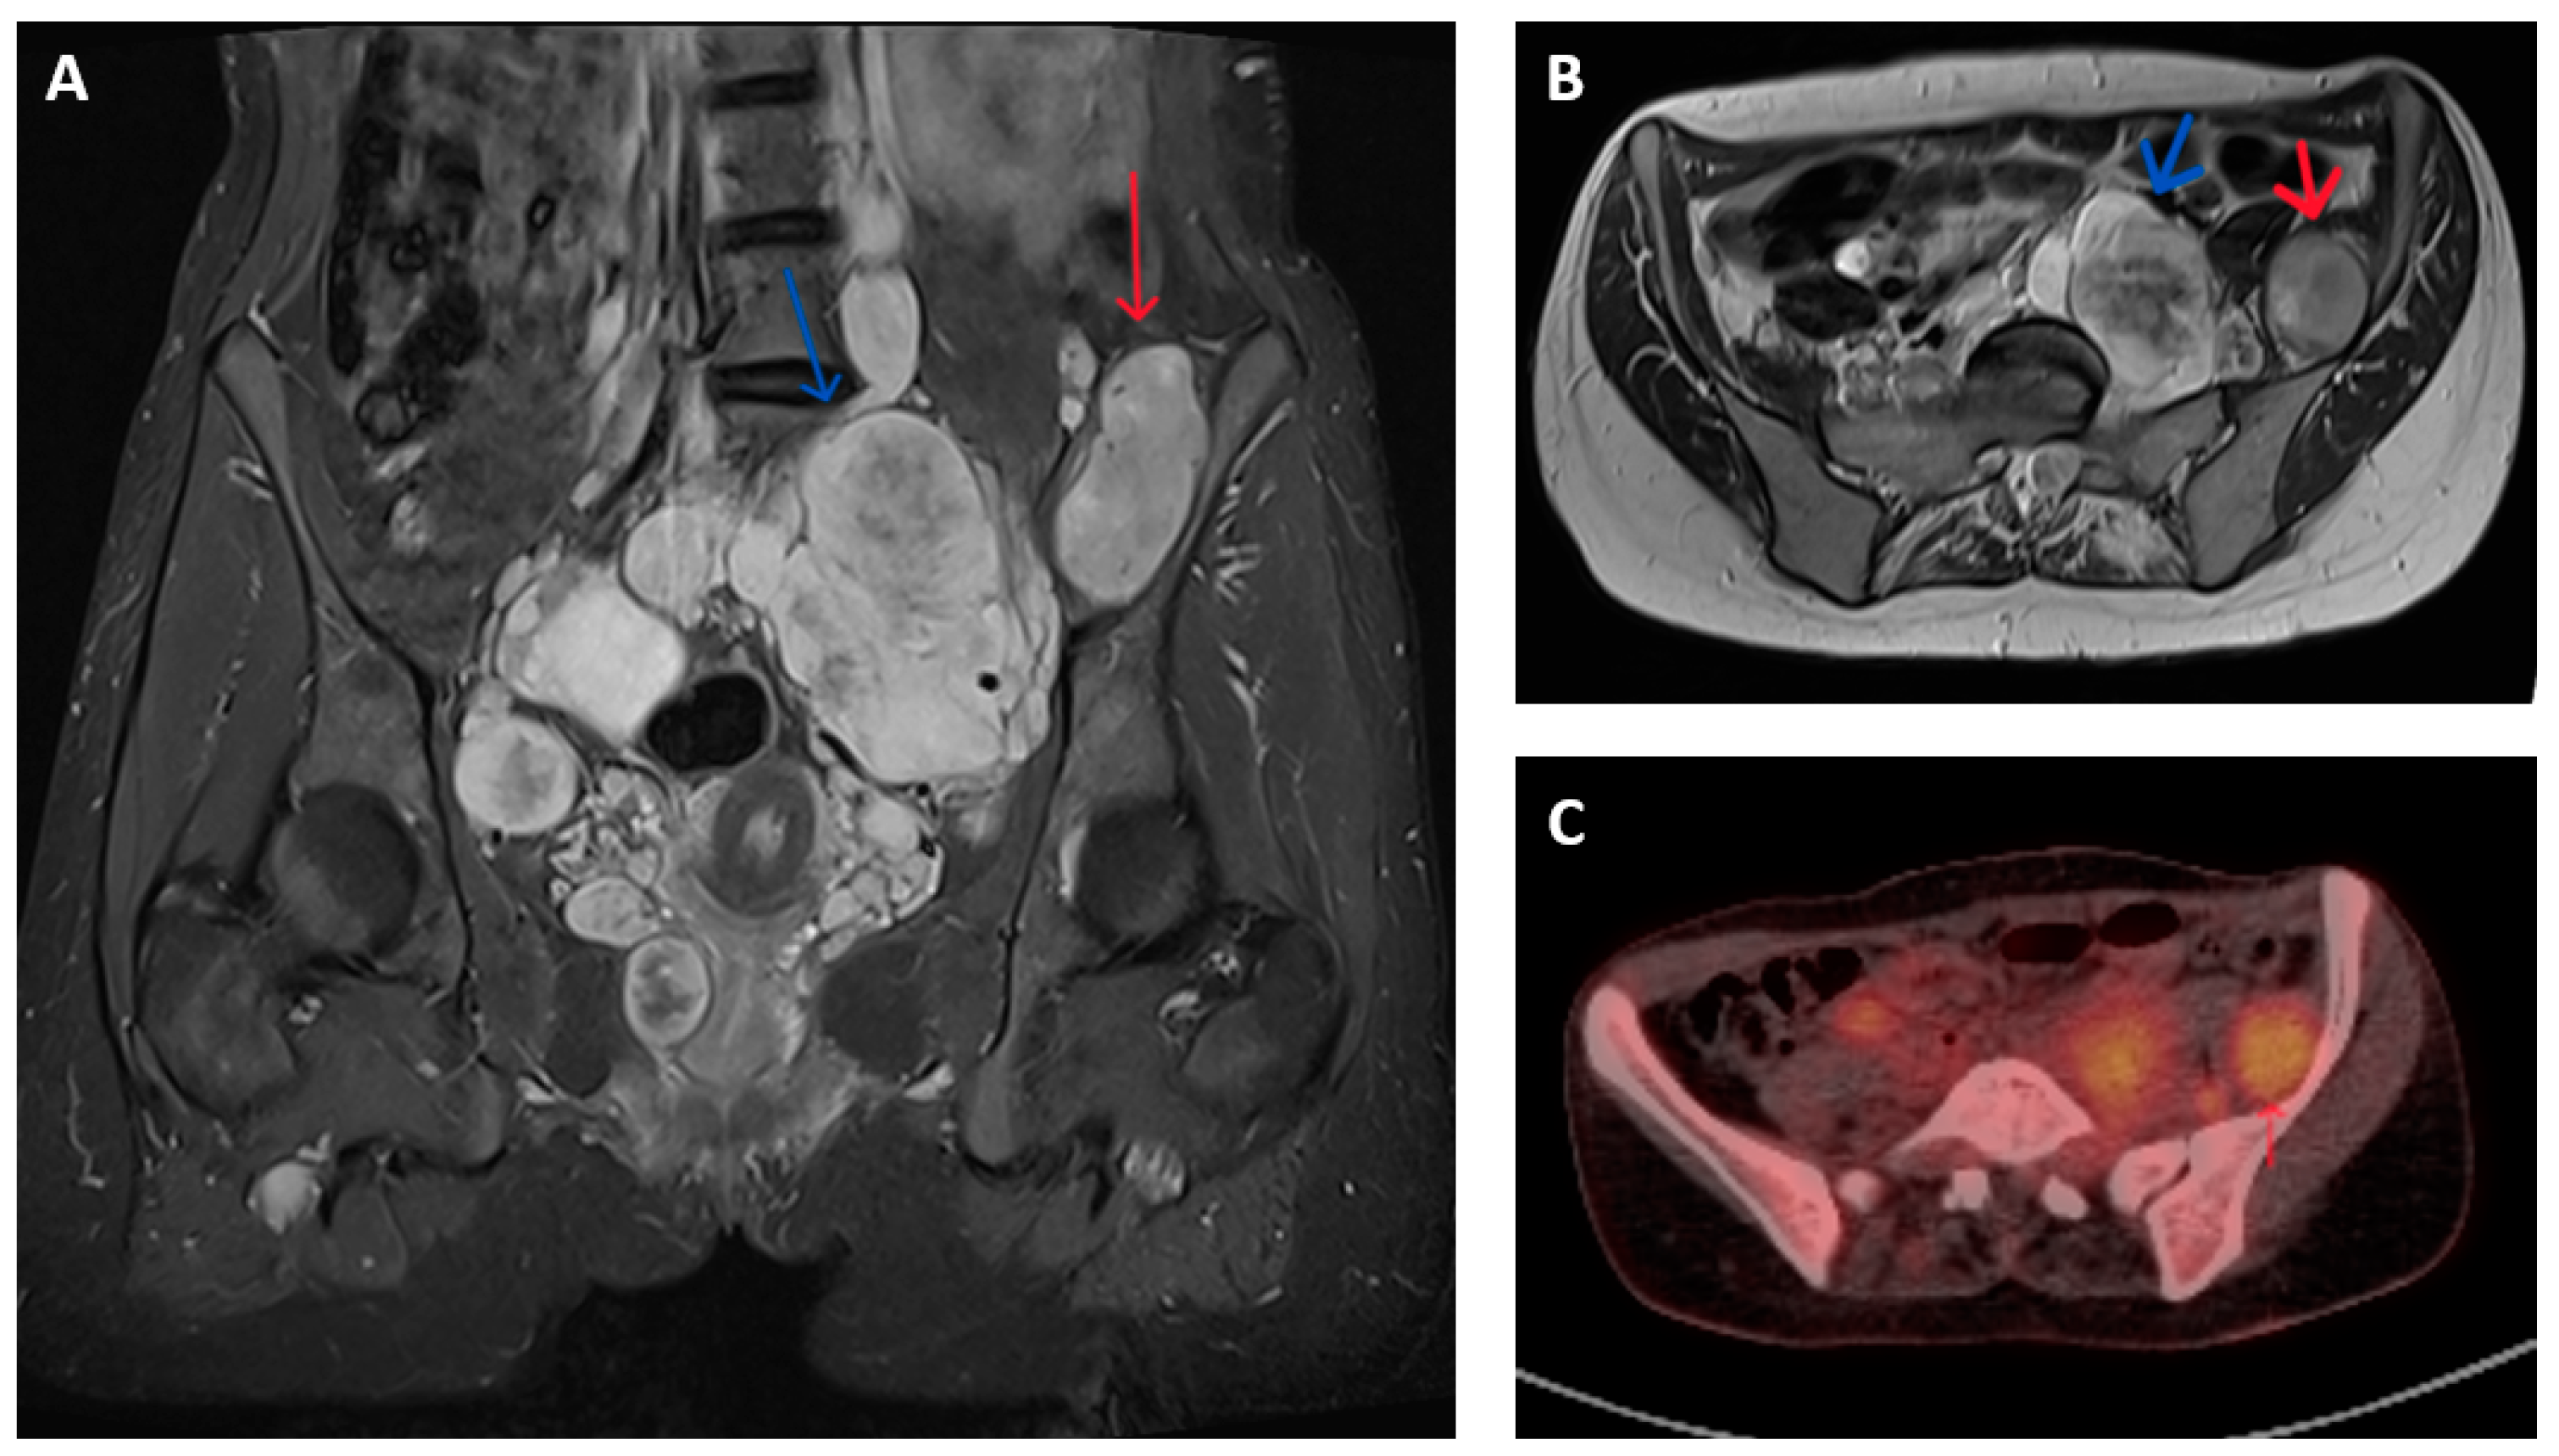

2.2. Imaging Characteristics

- Azizi, A.A.; Slavc, I.; Theisen, B.E.; Rausch, I.; Weber, M.; Happak, W.; Aszmann, O.; Hojreh, A.; Peyrl, A.; Amann, G.; et al. Monitoring of plexiform neurofibroma in children and adolescents with neurofibromatosis type 1 by [18F]FDG-PET imaging. Is it of value in asymptomatic patients? Pediatr. Blood Cancer 2018, 65, e26733. [Google Scholar] [CrossRef]

- Berzaczy, D.; Mayerhoefer, M.E.; Azizi, A.A.; Haug, A.R.; Senn, D.; Beitzke, D.; Weber, M.; Traub-Weidinger, T. Does elevated glucose metabolism correlate with higher cell density in Neurofibromatosis type 1 associated peripheral nerve sheath tumors? PLoS ONE 2017, 12, e0189093. [Google Scholar] [CrossRef]

- Fertitta, L.; Jannic, A.; Zehou, O.; Bergqvist, C.; Ferkal, S.; Moryousef, S.; Lerman, L.; Mulé, S.; Luciani, A.; Bapst, B.; et al. Whole-Body Positron Emission Tomography with 18F-Fluorodeoxyglucose/Magnetic Resonance Imaging as a Screening Tool for the Detection of Malignant Transformation in Individuals with Neurofibromatosis Type 1. J. Investig. Dermatol. 2024, 144, 1754–1761.e1. [Google Scholar] [CrossRef]